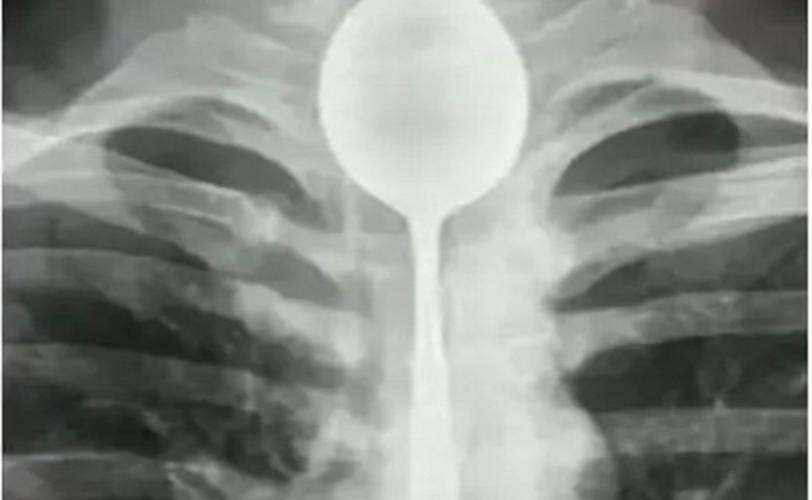

На Дніпропетровщині жінка намагалася за допомогою ложки спричинити блювотний рефлекс. Щось пішло не так, ложка застрягла у неї в горлі.

Прибувши на місце через 9 хвилин, медики побачили жінку, яка сиділа на стільці з ознаками зовнішньої кровотечі з порожнини рота. Вона розповіла, що погано почувалася, був дискомфорт у шлунку. Сусідка порекомендувала їй викликати блювоту, натиснувши на корінь язика пальцем. Спроба виявилася невдалою. Сусідка і тут не розгубилася і запропонувала використовувати для процедури ложку. Жінка так і зробила. Однак, коли вона поклала ложку на корінь язика, це викликало ковтальний рефлекс і столовий прилад опинився у неї в горлі. Диханню ложка не заважала, тому постраждала зателефонувала чоловікові, повідомивши про проблему.   Коханий швидко приїхав додому та” не розгубився” – взяв плоскогубці та витягнув ложку з горла. Наслідки не втішні – розірваний язик та пошкоджені мигдалики.